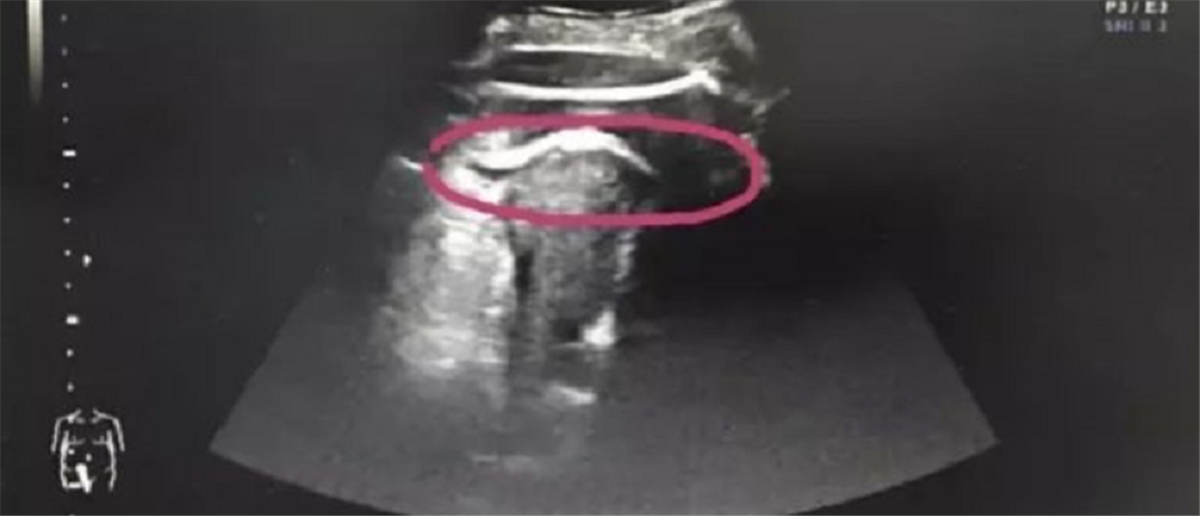

Η φωτογραφία της μήτρας που έδωσαν στη δημοσιότητα οι γιατροί:

Οι γιατροί δεν πίστευαν στα μάτια τους όταν την εξέτασαν κι αυτό γιατί διαπίστωσαν ότι η γυναίκα είχε υποστεί ρήξη μήτρας, η οποία προκλήθηκε από δυνατή κλωτσιά του εμβρύου!

Οι γιατροί του Πανεπιστημιακού Νοσοκομείου Shenzen της Κίνας, όπου ανέλαβαν την σπάνια αυτή υπόθεση, έκαναν γνωστό ότι στο σημείο όπου κλώτσησε το έμβρυο υπήρχε μια ουλή από χειρουργείο που είχε γίνει πριν ένα χρόνο.